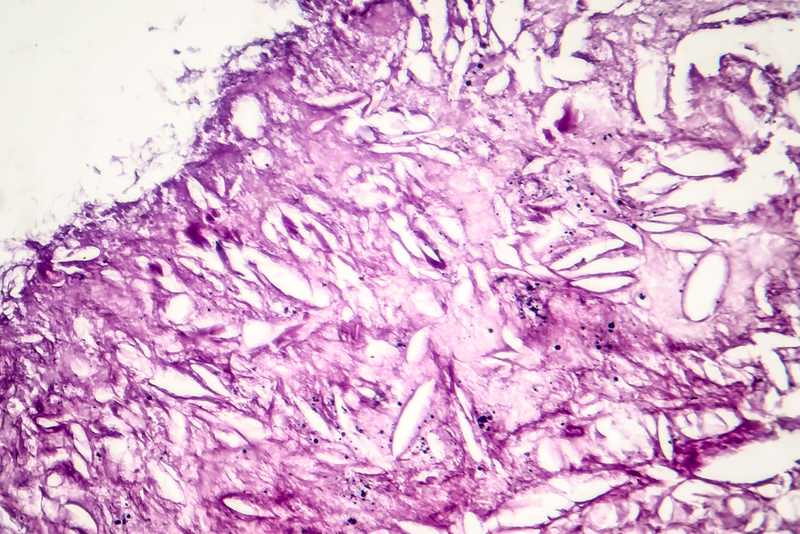

To make a melanoma vaccine, the researchers developed an antigen that includes a marker frequently overexpressed by melanoma cells, as well as an adjuvant, which creates a generalised danger signal for the immune system and boosts its response. Then, they tested different LbL microneedle film arrangements of antigen and adjuvant in immune cells derived from mice.

From these experiments, the researchers identified the optimal LbL microneedle structure that appears to activate immune cells directly accessible in the skin. In living mice, these cells could, in turn, migrate to the lymphatic system and recruit other immune cells to attack the melanoma tumour. The researchers now plan to test the patches on melanoma tumours in mice. "We are using low-cost chemistry and a simple fabrication scheme to transform vaccination," Hammond said. "Ultimately, we want to get a device approved and on the market," he added.